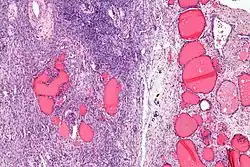

| Micrograph of a struma ovarii. Characteristic thyroid follicles are seen on the right, and ovarian stroma on the left. H&E stain. | |

-

Low magnification -